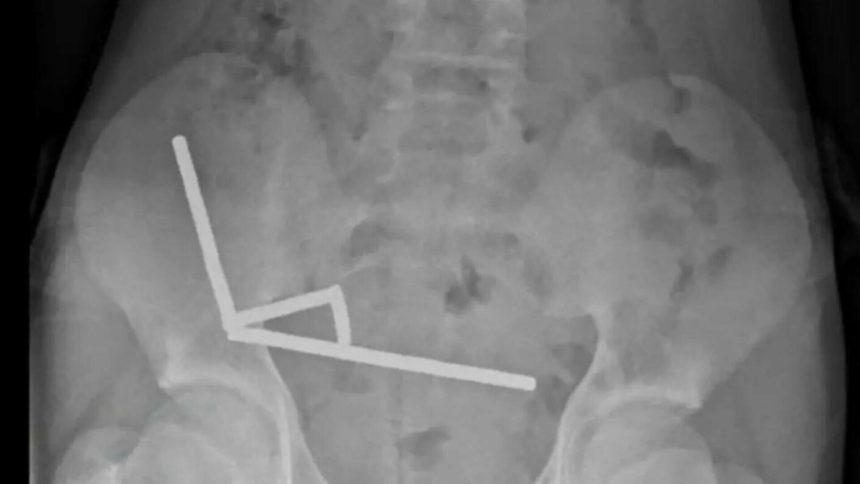

Imaginile radiologice au dezvăluit patru lanțuri magnetice blocate în diverse zone ale intestinului. Acestea s-au atras între ele, provocând blocaje și necroză intestinală, o condiție care i-a pus viața în pericol. Medicii au fost nevoiți să efectueze o intervenție chirurgicală complexă pentru a-i salva viața, îndepărtând o porțiune din intestin.